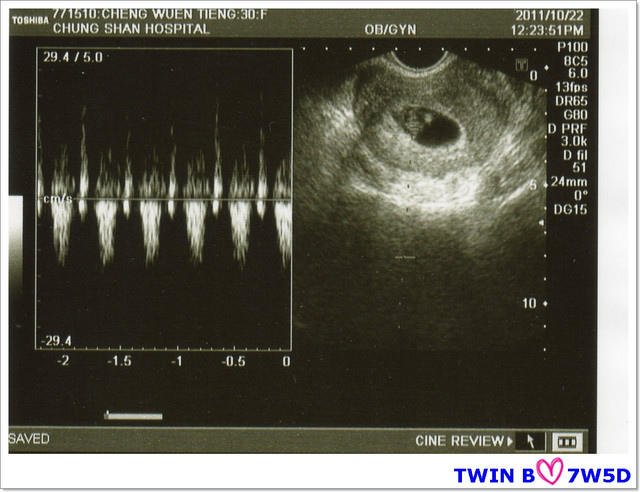

接著~要聽寶寶的心跳,羅醫生請我憋氣5秒,超音波室出現咚咚~咚咚~咚咚的心跳聲,

隔了一個禮拜,寶寶們都有乖乖的在媽咪的肚子裡長大喲:)